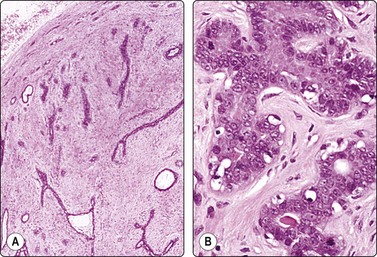

image image

Fig. 7.1 Radiation-induced atypia

(A) The epithelial cells in this irregular cluster show considerable nuclear enlargement, pleomorphism and hyperchromasia, but also some degenerative changes such as loss of nuclear structure (MGG, HP); (B) Corresponding tissue section (H&E, IP).